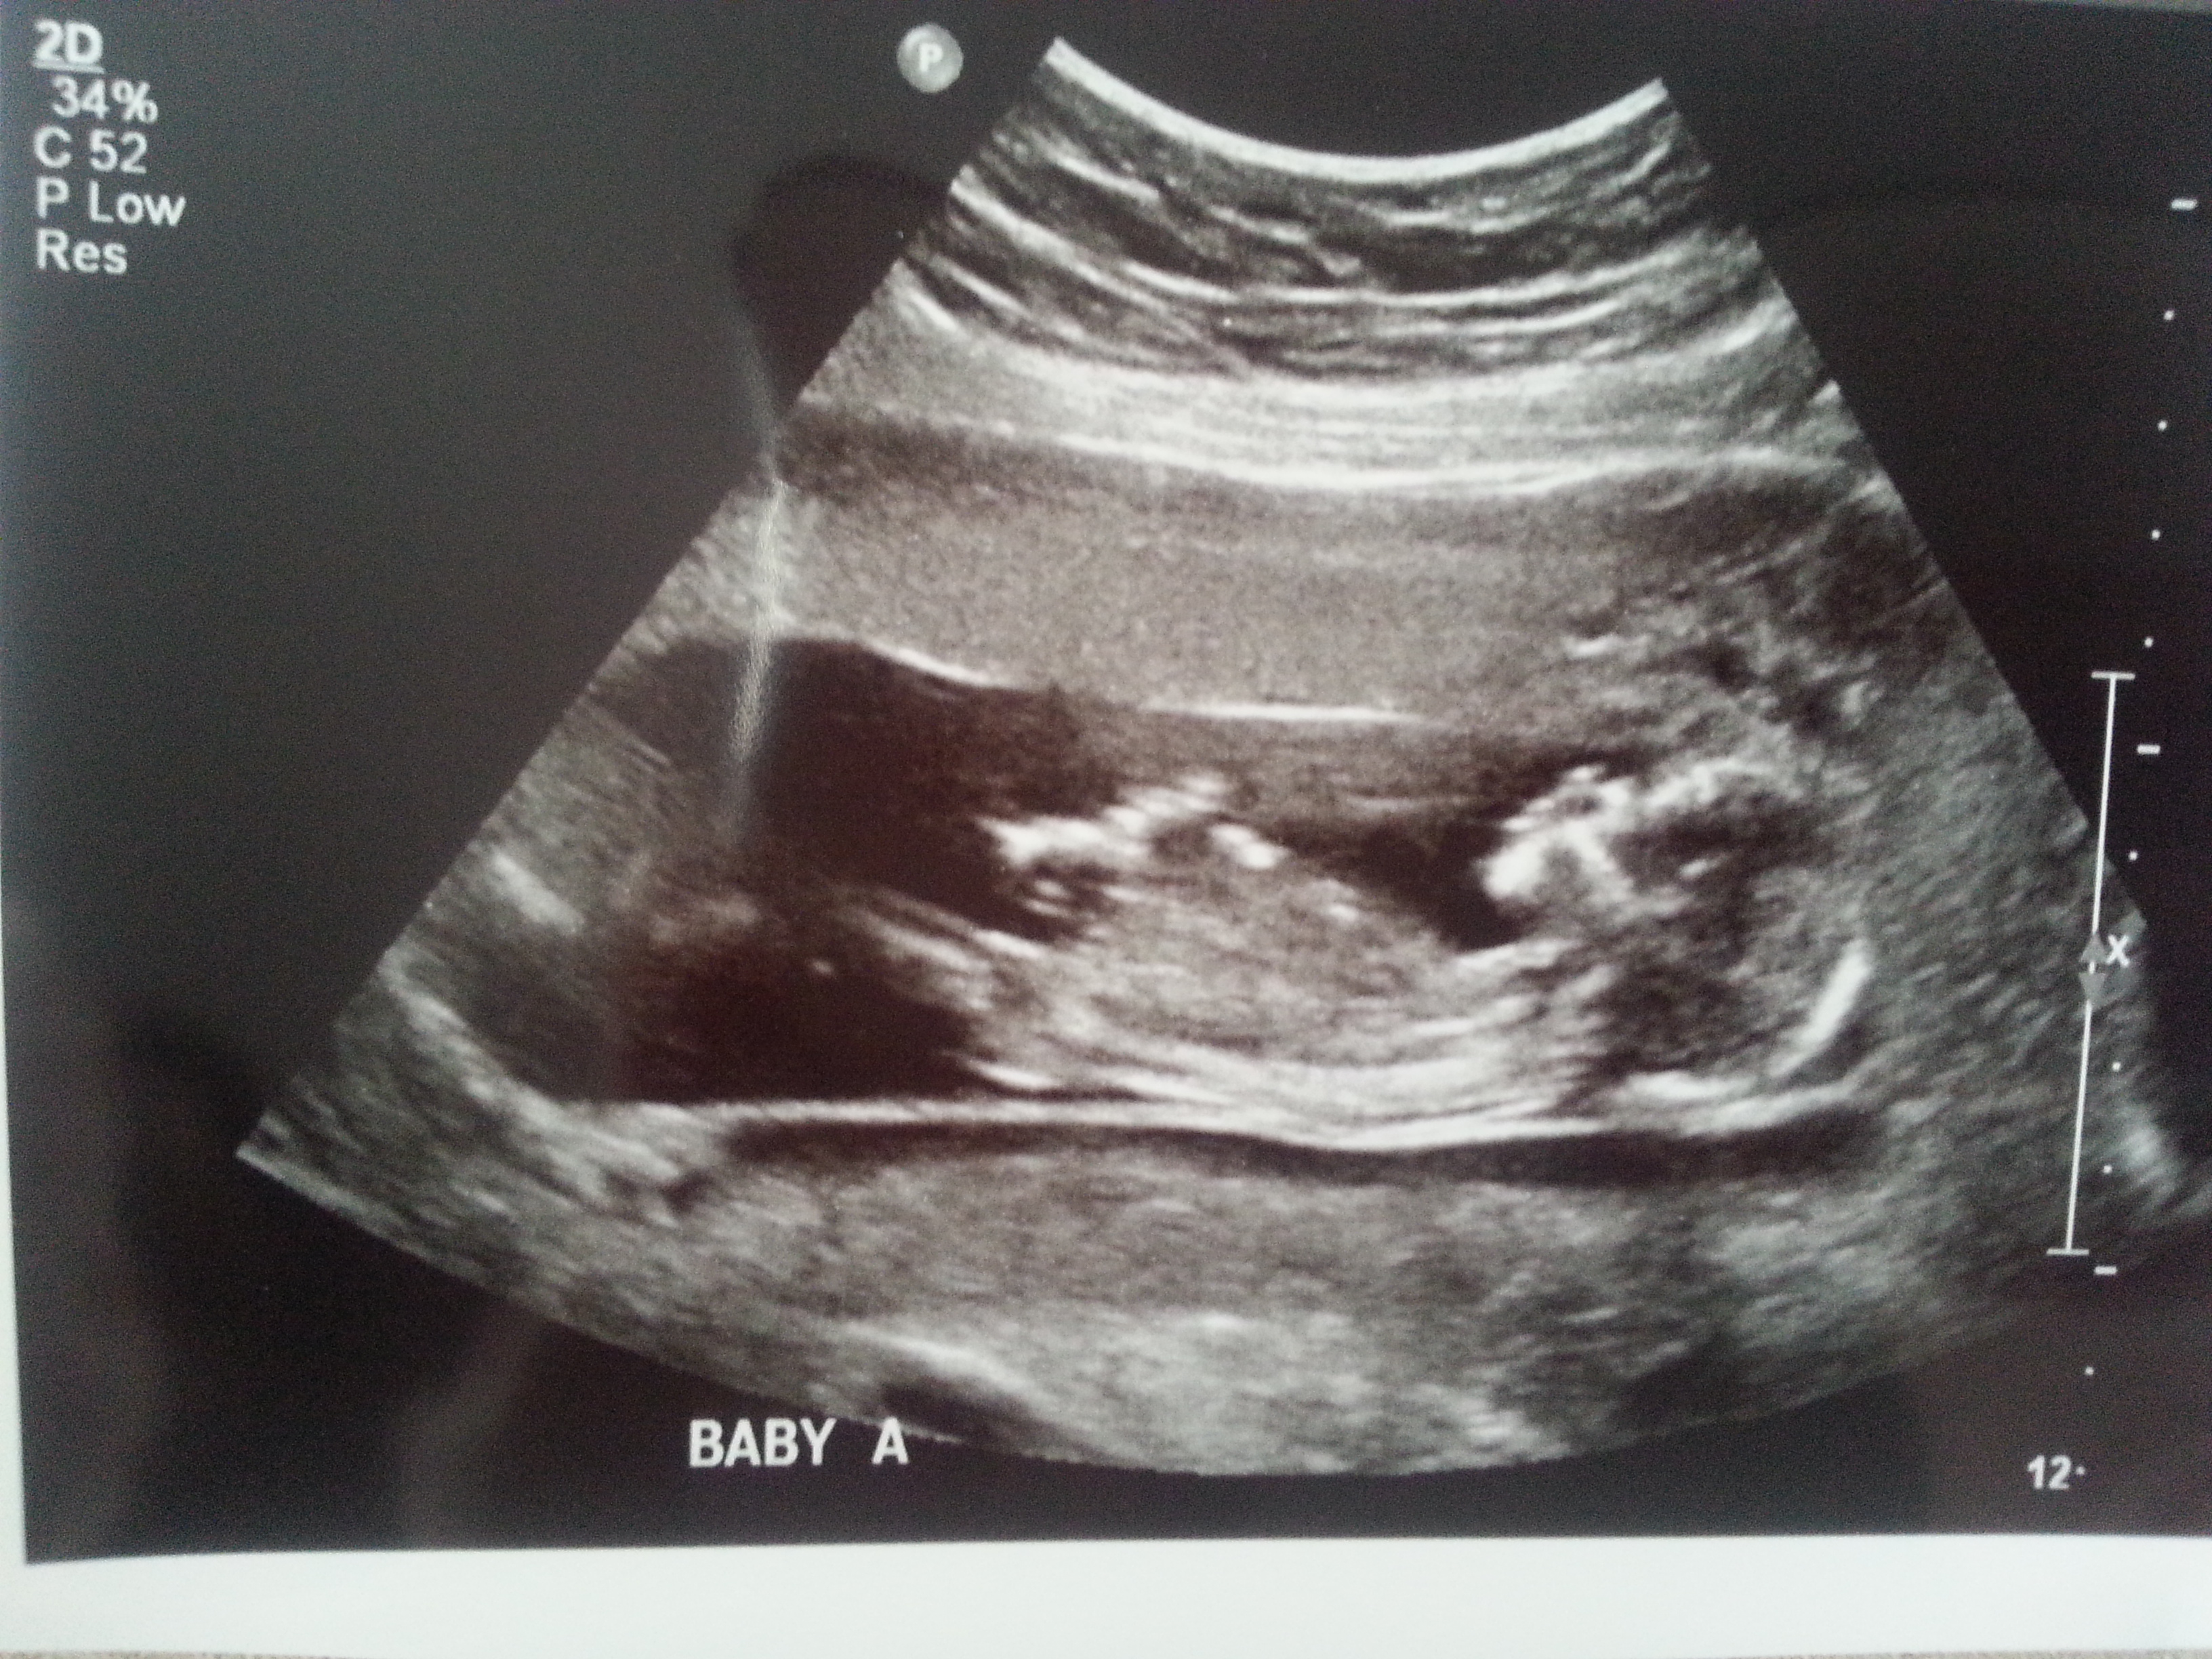

I was 12weeks 6 days and measuring 13weeks 3 days.

Attachment 23434

Maybe boy/girl. Not the best shots though!

Thank you, they noth were moving soo much it was hard to get a good shot. I go on Monday for my NT scan this one was done bc I have the stomach bug and am in the Hospital. We did look at their potty shots but still early and I have no idea what to look for at that age lol..

I think B is a boy and A is a girl.

I think B is a boy, A could go either way but I lean boy.